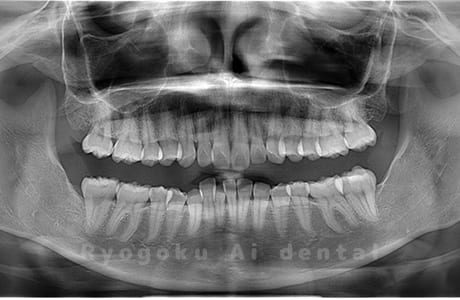

Case03

-

- 原因

- 上顎、下顎の親知らず

- 治療内容

- 上下4本の親知らずを抜歯したケースです。

<リスク・副作用>

手術後は痛み、腫れ、痺れなどの副作用が生じる場合があります。